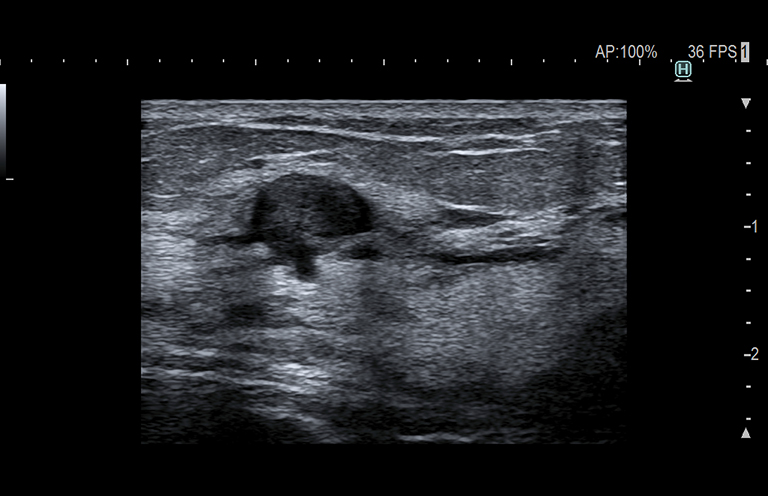

Aplicación: Mama

Función/análisis: Modo B

Comentarios: Mama